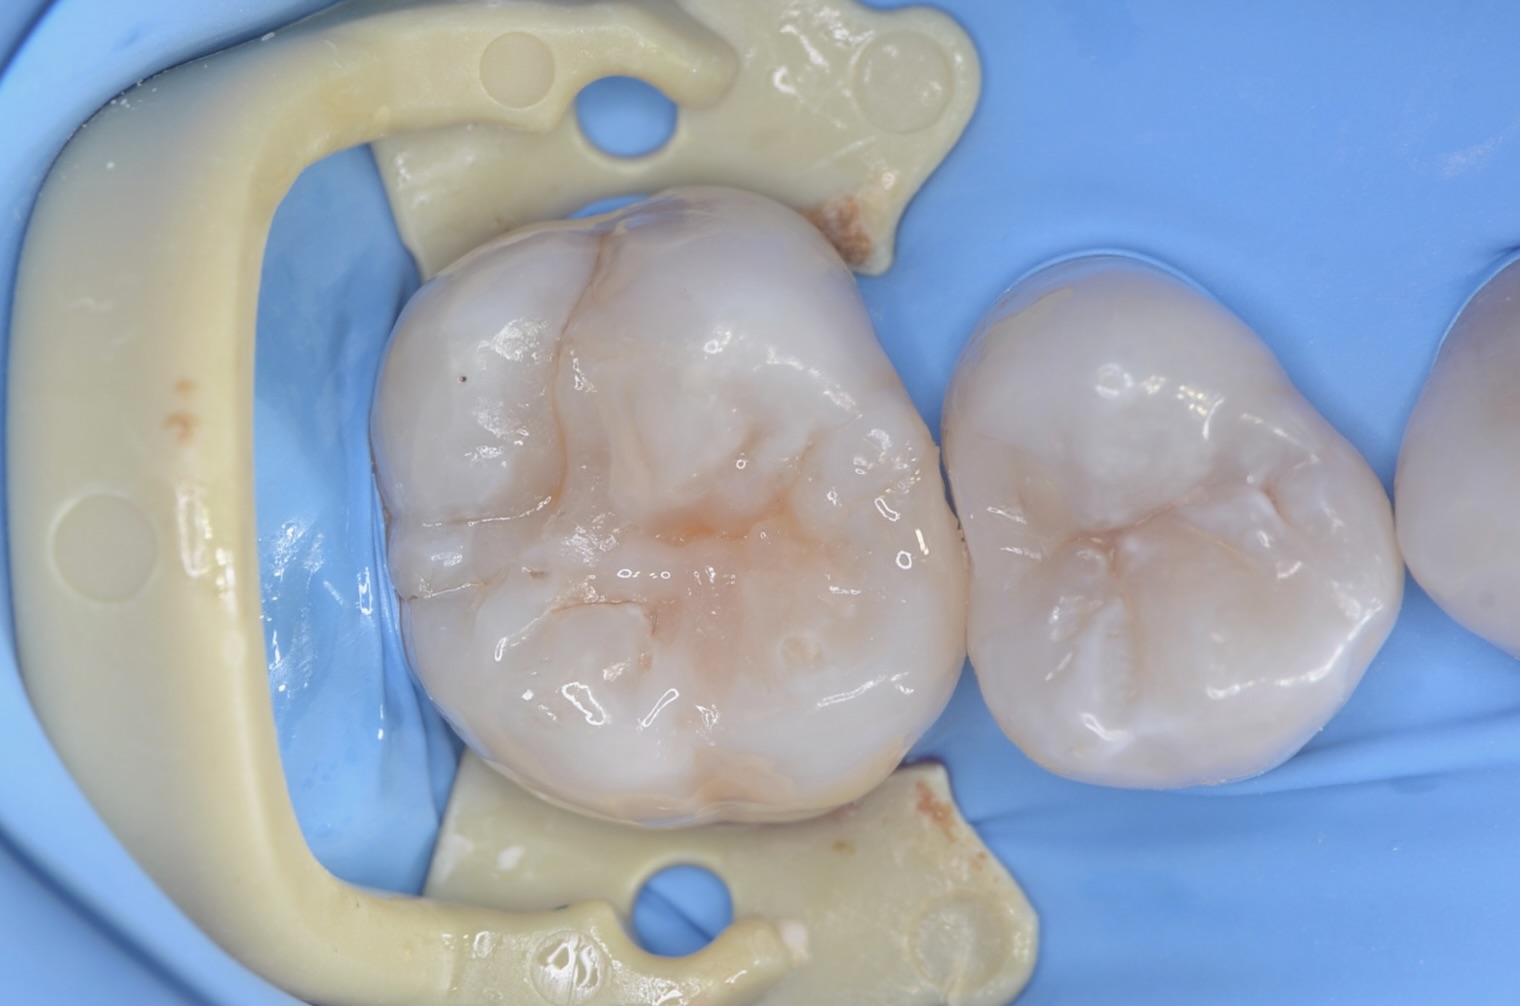

After

ダイレクトボンディング終了

天然の歯の形態を模倣してレジンを充填します。 -

噛み合わせの調整と研磨後

研磨をしっかり丁寧にすることで、レジンと歯質の段差を修正し、虫歯になりにくくします。